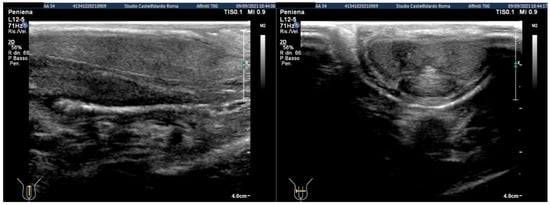

| 1 | 31 years | Chronic prostatitis and associated anxious and depressive state. | Distal third | (A) 15.1 × 12.1 × 3.7 mm volume = 353 mm3 (B) No plaque detected | (A) 10-degree ventral curvature + 15-degree left curvature (B) None | VAS score = 8 Pain disappeared after 12 months | 26 > 27 | 30 months | Orally: propolis 600 mg + bilberry 160 mg + silymarin 400 mg + ginkgo biloba 250 mg + L-carnitine 1000 mg + coenzyme Q10 100 mg + Boswellia 200 mg + Vitamin E 30 mg/daily/for 30 months + topically: diclofenac gel 4%/2× daily for 30 months Note: The patient refused periplaque penile injections with pentoxifylline |